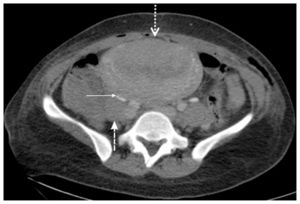

On the second postoperative day, the mother exhibited pain in the right iliac fossa and pyrexia (38°C). An abdominal examination revealed right lower quadrant tenderness that radiated to the ipsilateral flank, rebound tenderness, and right lumbar pain. The patient’s white blood cell count was 1100/μl, and a blood coagulation profile showed an activated partial thromboblastin time of 37 s (normal value: 25–40), a derived fibrinogen level of 445 mg/dl (normal value: 200–450), and a D-dimer level of 865 μ/mm3 (normal value: 0–200). An abdominal computed tomographic image exhibited extrinsic compression of the ureter by a hypodense filling defect within the right ovarian vein, which is characteristic of ovarian vein thrombosis and grade III–IV hydronephrosis (Figures 2, 3, and 4). Thus, the patient was treated with a low-molecular weight heparin coagulant (nadroparin 3800 IU, 0.6 ml every 12 h). Three days after the beginning of this therapy, color Doppler ultrasonography revealed a good vascular flow in right ovary, recanalization of the ovarian vein, and a reduction in the amount of fluid in the abdomen. At this point in time, the ureter was still dilated by extrinsic compression; however, a week later, ultrasonography showed normal-size ureter. The patient’s coagulation profile was within normal ranges in the following days.